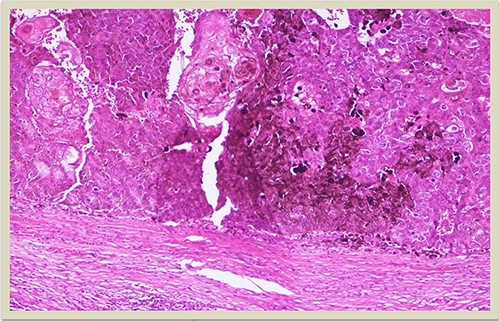

A 69-year-old man was admitted to our hospital with a nodular skin tumor of the back (Fig. 1). The patient had no ongologic history. We performed excisional biopsy that revealed collision tumor. The collision tumor consisted of mixed melanosquamous tumor (dermal squamomelanocytic tumor) together with BCC (Fig. 2). The BCC was superficial spreading. The mixed element contained squamous cell carcinoma of well/moderately differentiated and a neoplasm with melanotic characteristics, which due to cell atypia, presence of mitoses and high index of cell proliferation (Ki67: 80%) was described as melanoma (Fig. 3). Diagnosis of the melanotic and the squamous element was confirmed with immunohistochemistry (Figs 4 and 5).

HMB45 × 4: HMB45 immunostain highlights the malignant melanocytic component ( ×10 magnification).

Histologically the collision tumor involves two different and distinct entities. There is no interaction between the tumor cells of the two different neoplasms. The paradox in our case is that the melanotic cells were admixed with squamous cells. The histopathologic findings of the combined tumor were confirmed with immunohistochemistry. Squamous element was confirmed from the positivity of the stains: AE1/AE3, EMA and CK5. Melanotic element was also confirmed with the following stains: Vimentin, S-100, MART-1(Melan-A) and HMB45. Histologic findings and immunohistochemical stains confirmed the combined melanosquamous neoplasm in the collision tumor, which does not seem to involve epidermis. Reviewing the literature, we did not find any other case of a combined neoplasm in a collision formation.